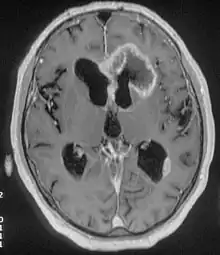

There are many different causes of frontal lobe epilepsy ranging from genetics to head trauma that result in lesions in the frontal lobes.[4] Although frontal lobe epilepsy is often misdiagnosed, tests such as prolonged EEG monitoring, video EEG and/or an MRI scan of the frontal lobes can be administered in order to reveal the presence of a tumor or vascular malformation.[4] Unlike most epileptic EEGs, the abnormalities in FLE EEGs precede the physical onset of the seizure and aid in localization of the seizure's origin.[4] Medications such as anti-epileptic drugs can typically control the onset of seizures, however, if medications are ineffective the patient may undergo surgery to have focal areas of the frontal lobe removed.[4]

Neuroimaging for diagnosis

Advancements in technology, has given rise to newer, more efficient methods of diagnosis, most prominent being in the domain of neuroimaging.[8] The high spatial resolution from fMRI has implications on certain brain regions contributing to memory.[8] The usage of task fMRI for examination of memory or other higher cognitive networks may also be used to predict ictal onset zone(s) in patients with FLE, giving the advantage of refinement of patient-specific analyses.[8] The use of multi-modal approaches in association with neuroimaging techniques like fMRI and MEG or EEG will be informative in characterizing atypical functional brain networks in FLE.[8] But, difficulty remains in the evaluation of potential compensatory mechanisms between patients with FLE with normal and impaired memory, without properly characterizing transfer of information during memory tasks.[8]